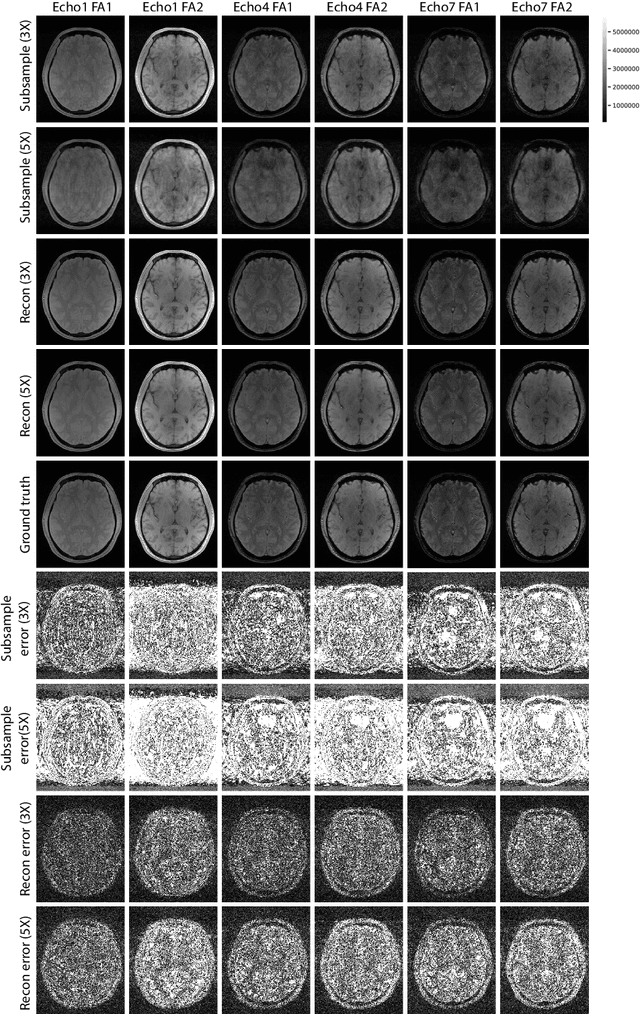

Abstract:Multi-contrast MRI images provide complementary contrast information about the characteristics of anatomical structures and are commonly used in clinical practice. Recently, a multi-flip-angle (FA) and multi-echo GRE method (MULTIPLEX MRI) has been developed to simultaneously acquire multiple parametric images with just one single scan. However, it poses two challenges for MULTIPLEX to be used in the 3D high-resolution setting: a relatively long scan time and the huge amount of 3D multi-contrast data for reconstruction. Currently, no DL based method has been proposed for 3D MULTIPLEX data reconstruction. We propose a deep learning framework for undersampled 3D MRI data reconstruction and apply it to MULTIPLEX MRI. The proposed deep learning method shows good performance in image quality and reconstruction time.